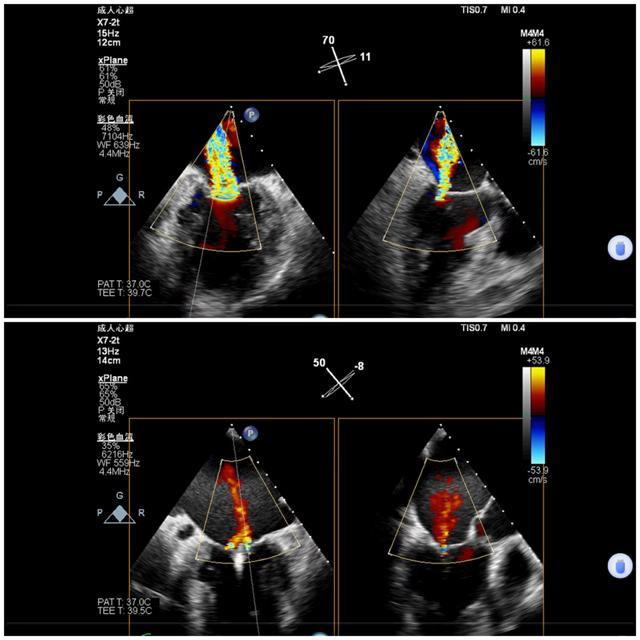

7月9日上午心内科联合麻醉科、胸外科等多学科,共同为陈奶奶开展手术,术前二尖瓣大量反流,反流程度5+,肺静脉反流明显,术后二尖瓣少量反流,反流程度1+,肺静脉反流消失,手术顺利结束。

手术前后二尖瓣反流